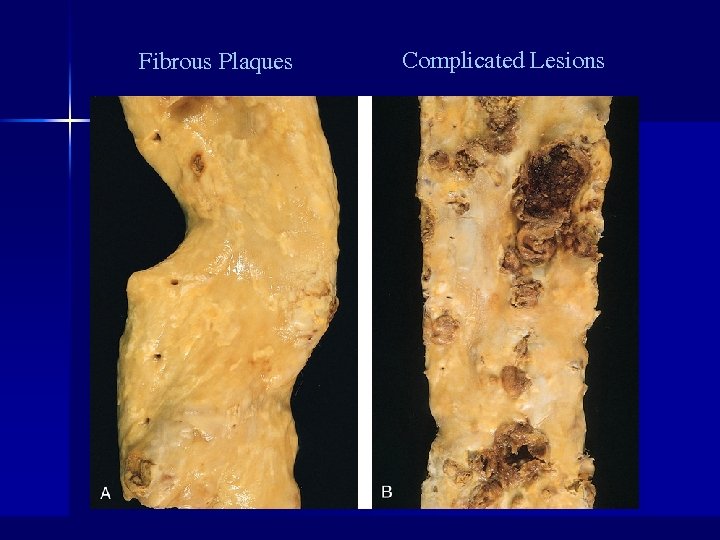

General Comments n Arteriosclerosis – Thickening and loss of elasticity of arterial walls – Hardening of the arteries – Greatest morbidity and mortality of all human diseases n Two major processes in plaque formation: – Intimal thickening – Lipid accumulation

Summary of Atherosclerotic Process n n n n n Multifactorial process (risk factors) Initiated by endothelial dysfunction Up regulation of endothelial and leukocyte adhesion molecules Macrophage diapedesis LDL transcytosis LDL oxidation Foam cells Recruitment and proliferation of smooth muscle cells (synthesis of connective tissue proteins) Formation and organization of arterial thrombi

Fibrous Plaques Complicated Lesions

Complicated Lesions